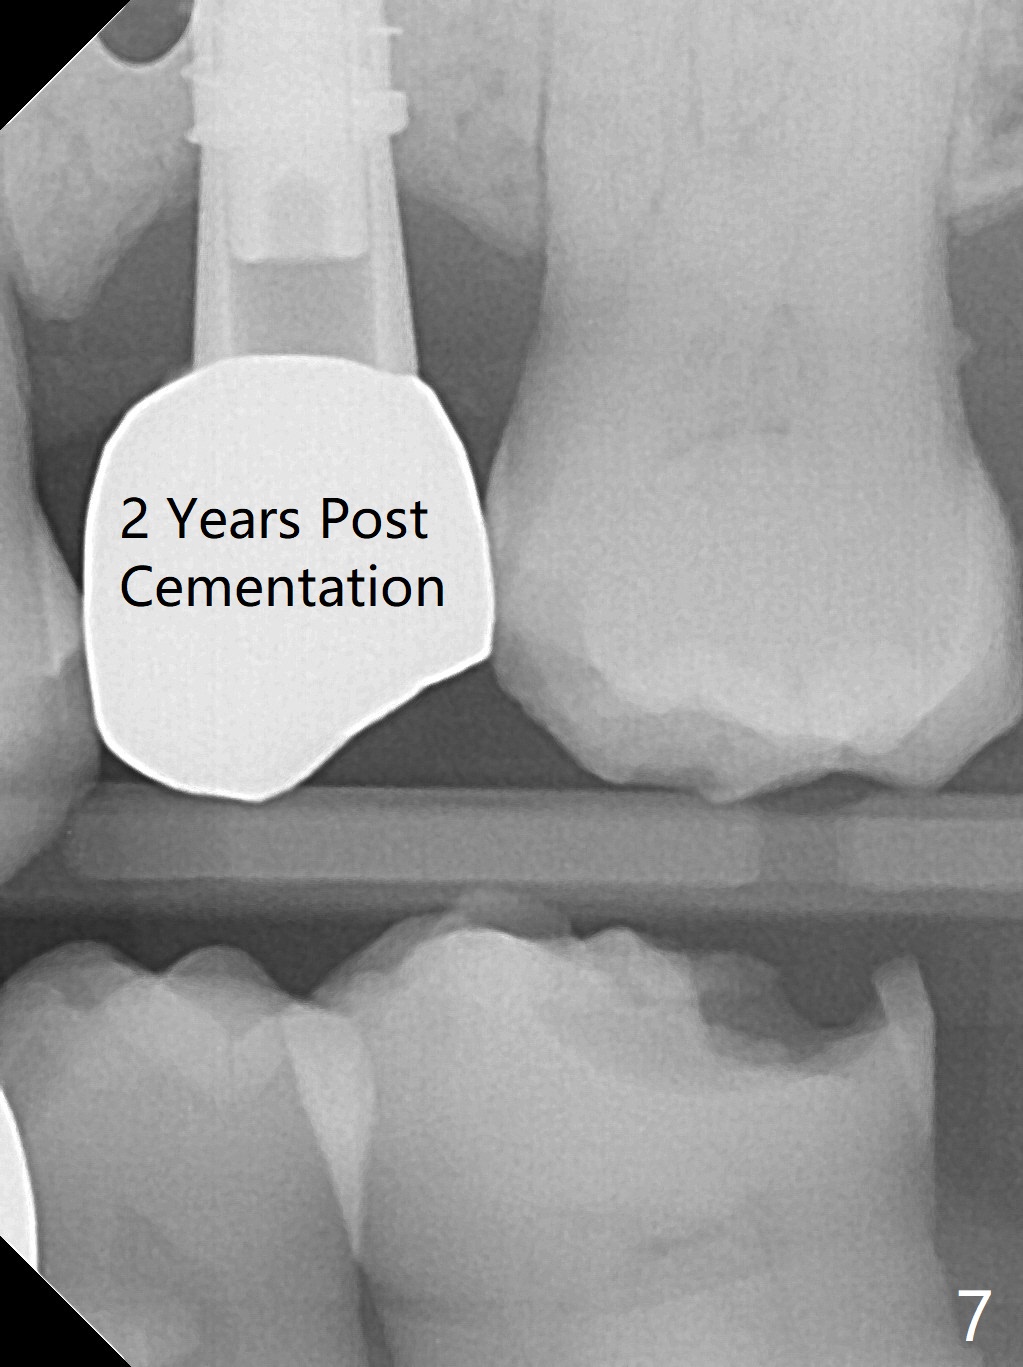

A 74-year-old man has diabetes. Implant osteointegration appears to be slow at #4, while the implant at #28 failed once. He requests implant at #13 (Fig.1). It seems that the bone is wide enough (8 mm, Fig.2 (CT coronal section) (P: palatal)) to hold a 4 mm implant (Fig.3 (axial section)). Since bone density is low at the coronal (100-200 units) and middle (50-100 units) segments (Fig.2), bone condensation will be beneficial. To facilitate wound healing, flapless approach is adopted using 1.6 mm pilot drill (Fig.4), followed by 1.4/2.6 mm bone expander. In fact there is resistance to expansion in the zone 1. Magic expander (3.0 mm) is also tried with difficulty. It appears that bone density is higher than expected. The second portion of Magic Surgical Kit is then used: 3.3 mm Magic Drill for 15 mm (gingival level, followed by Final Drill). A 4x13 mm IBS implant is seated incompletely. The osteotomy is further enlarged by 3.8 mm Magic Drill for 11 mm and deepened with 3 mm drill until 18 mm. Finally the implant is placed at a satisfactory level with insertion torque > 50 Ncm (Fig.5). A 4.5x4(3) mm abutment is placed and periodontal dressing is applied. The patient chooses to return for impression 6 months postop (Fig.6). The abutment changes to a 4x4(4) mm one. The crown is recemented nearly 2 years post cementation, which is related to distal and deep placement of the implant and bruxism (Fig.7).